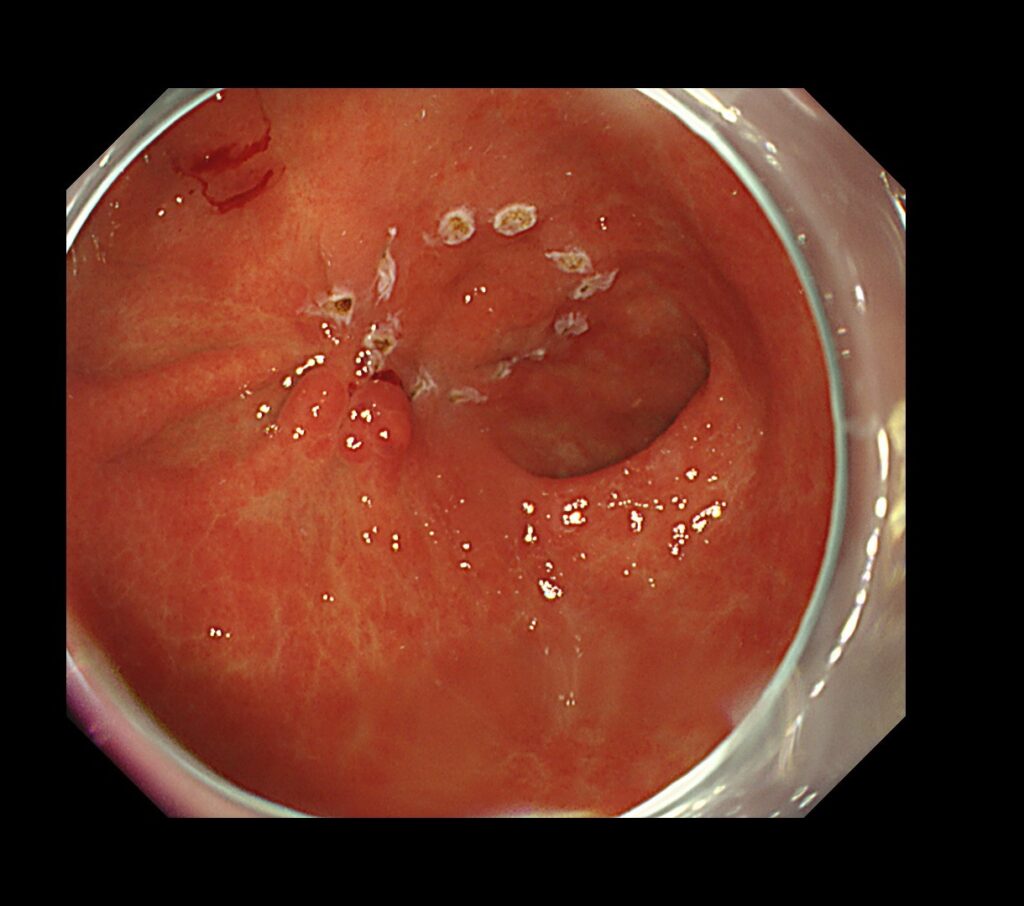

前庭部前壁に易出血領域を認めます。

拡大観察で癌血管を全周性に視認できます。やはり、癌部:茶色、非癌部:緑色として観察されます。